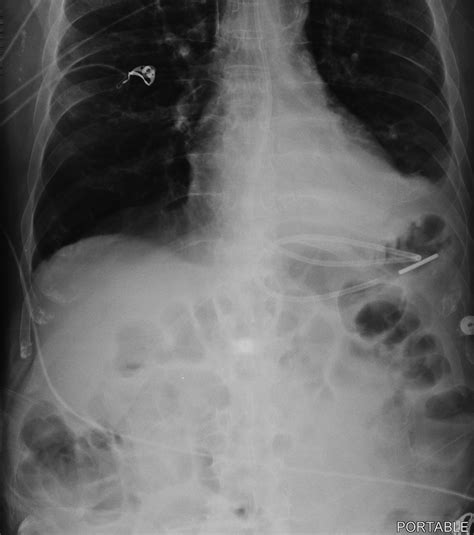

• Tube Advancement: Continue to advance the tube until it reaches the desired location in the small intestine. This can be confirmed using various methods, such as auscultation, pH testing, or X-ray.

• Confirmation of Placement: Use a stethoscope to listen for air insufflation as the tube is advanced. Alternatively, use pH indicator strips to check the pH of the aspirate, which should be alkaline (pH > 6) in the small intestine.

• dobhoff tube placement x ray